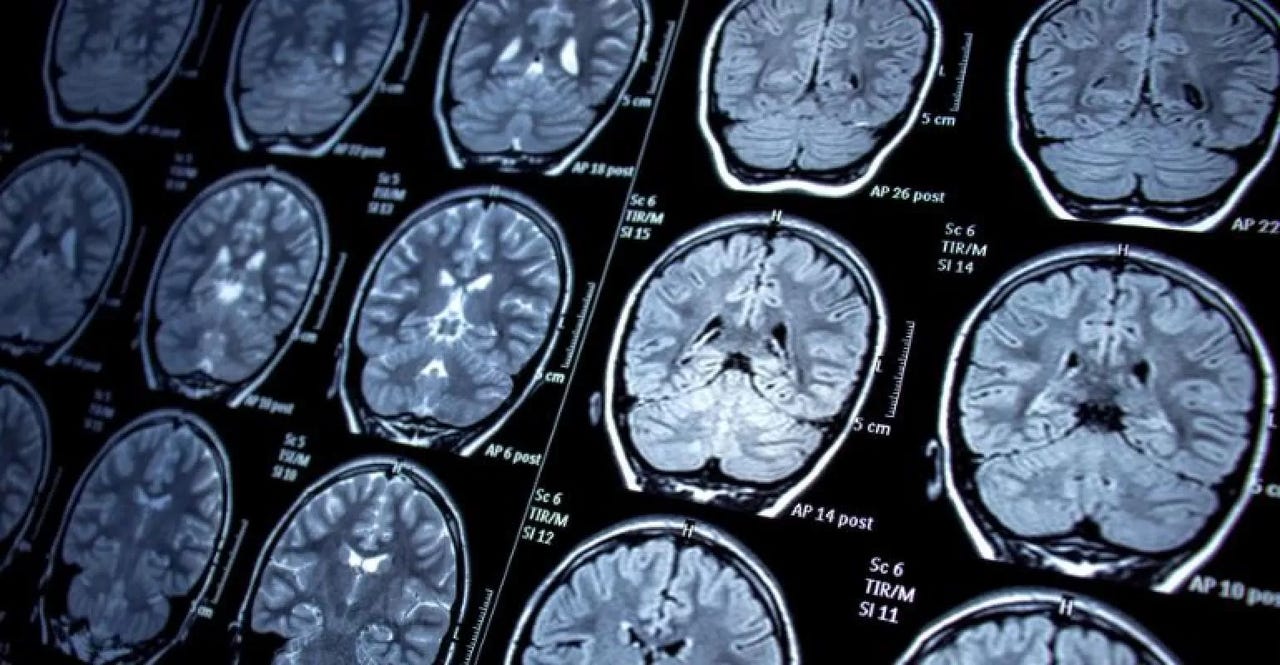

Epilepsy is a chronic neurological disorder characterised by recurrent seizures, which result from excessive electrical discharges in the brain. These seizures can vary in severity and frequency, leading to physical problems, psychological conditions, and an increased risk of premature death.

A diagnostic method that also involves the use of electrodes is Stereo-EEG (SEEG). Electrodes are also implanted in the brain to accurately record abnormal signals that cause seizures. They pinpoint the precise source of epileptic seizures in the brain, helping the surgeon decide if a surgical intervention would be beneficial and plan for it accordingly.